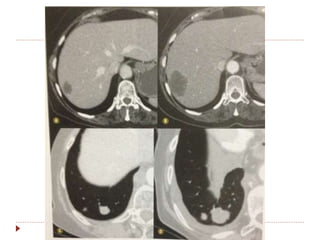

RECIST

 Limitações

 O critério morfológico não contempla mudança de textura

de lesão (escavação, necrose, ...)

 Diferenciação de lesão residual/cicatricial.

 Não permite avaliar lesões tratadas com radiofrequencia /

crioablasão, com área tratada maior que o tumor.

RECIST  Limitações  Ocritério morfológico não contempla mudança de textura de lesão (escavação, necrose, ...)  Diferenciação de lesão residual/cicatricial.  Não permite avaliar lesões tratadas com radiofrequencia / crioablasão, com área tratada maior que o tumor.